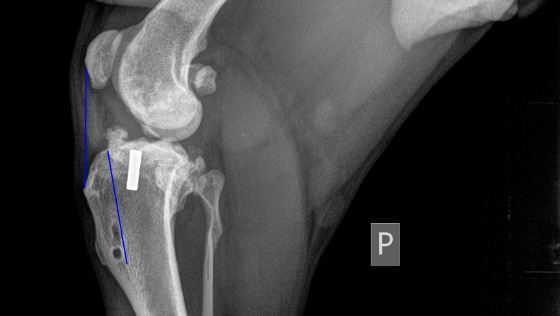

Zarówno artroskopia, jak i stabilizacja łokcia udały się doskonale, wszystko poszło gładko i bez komplikacji :)

Całkowity koszt operacji wyniósł 2 089,68 zł, a składały się na niego - zaliczka w wysokości 3 000 KC (516,47 zł) i faktura za sam zabieg 9 983,00 KC (1573,21 zł)